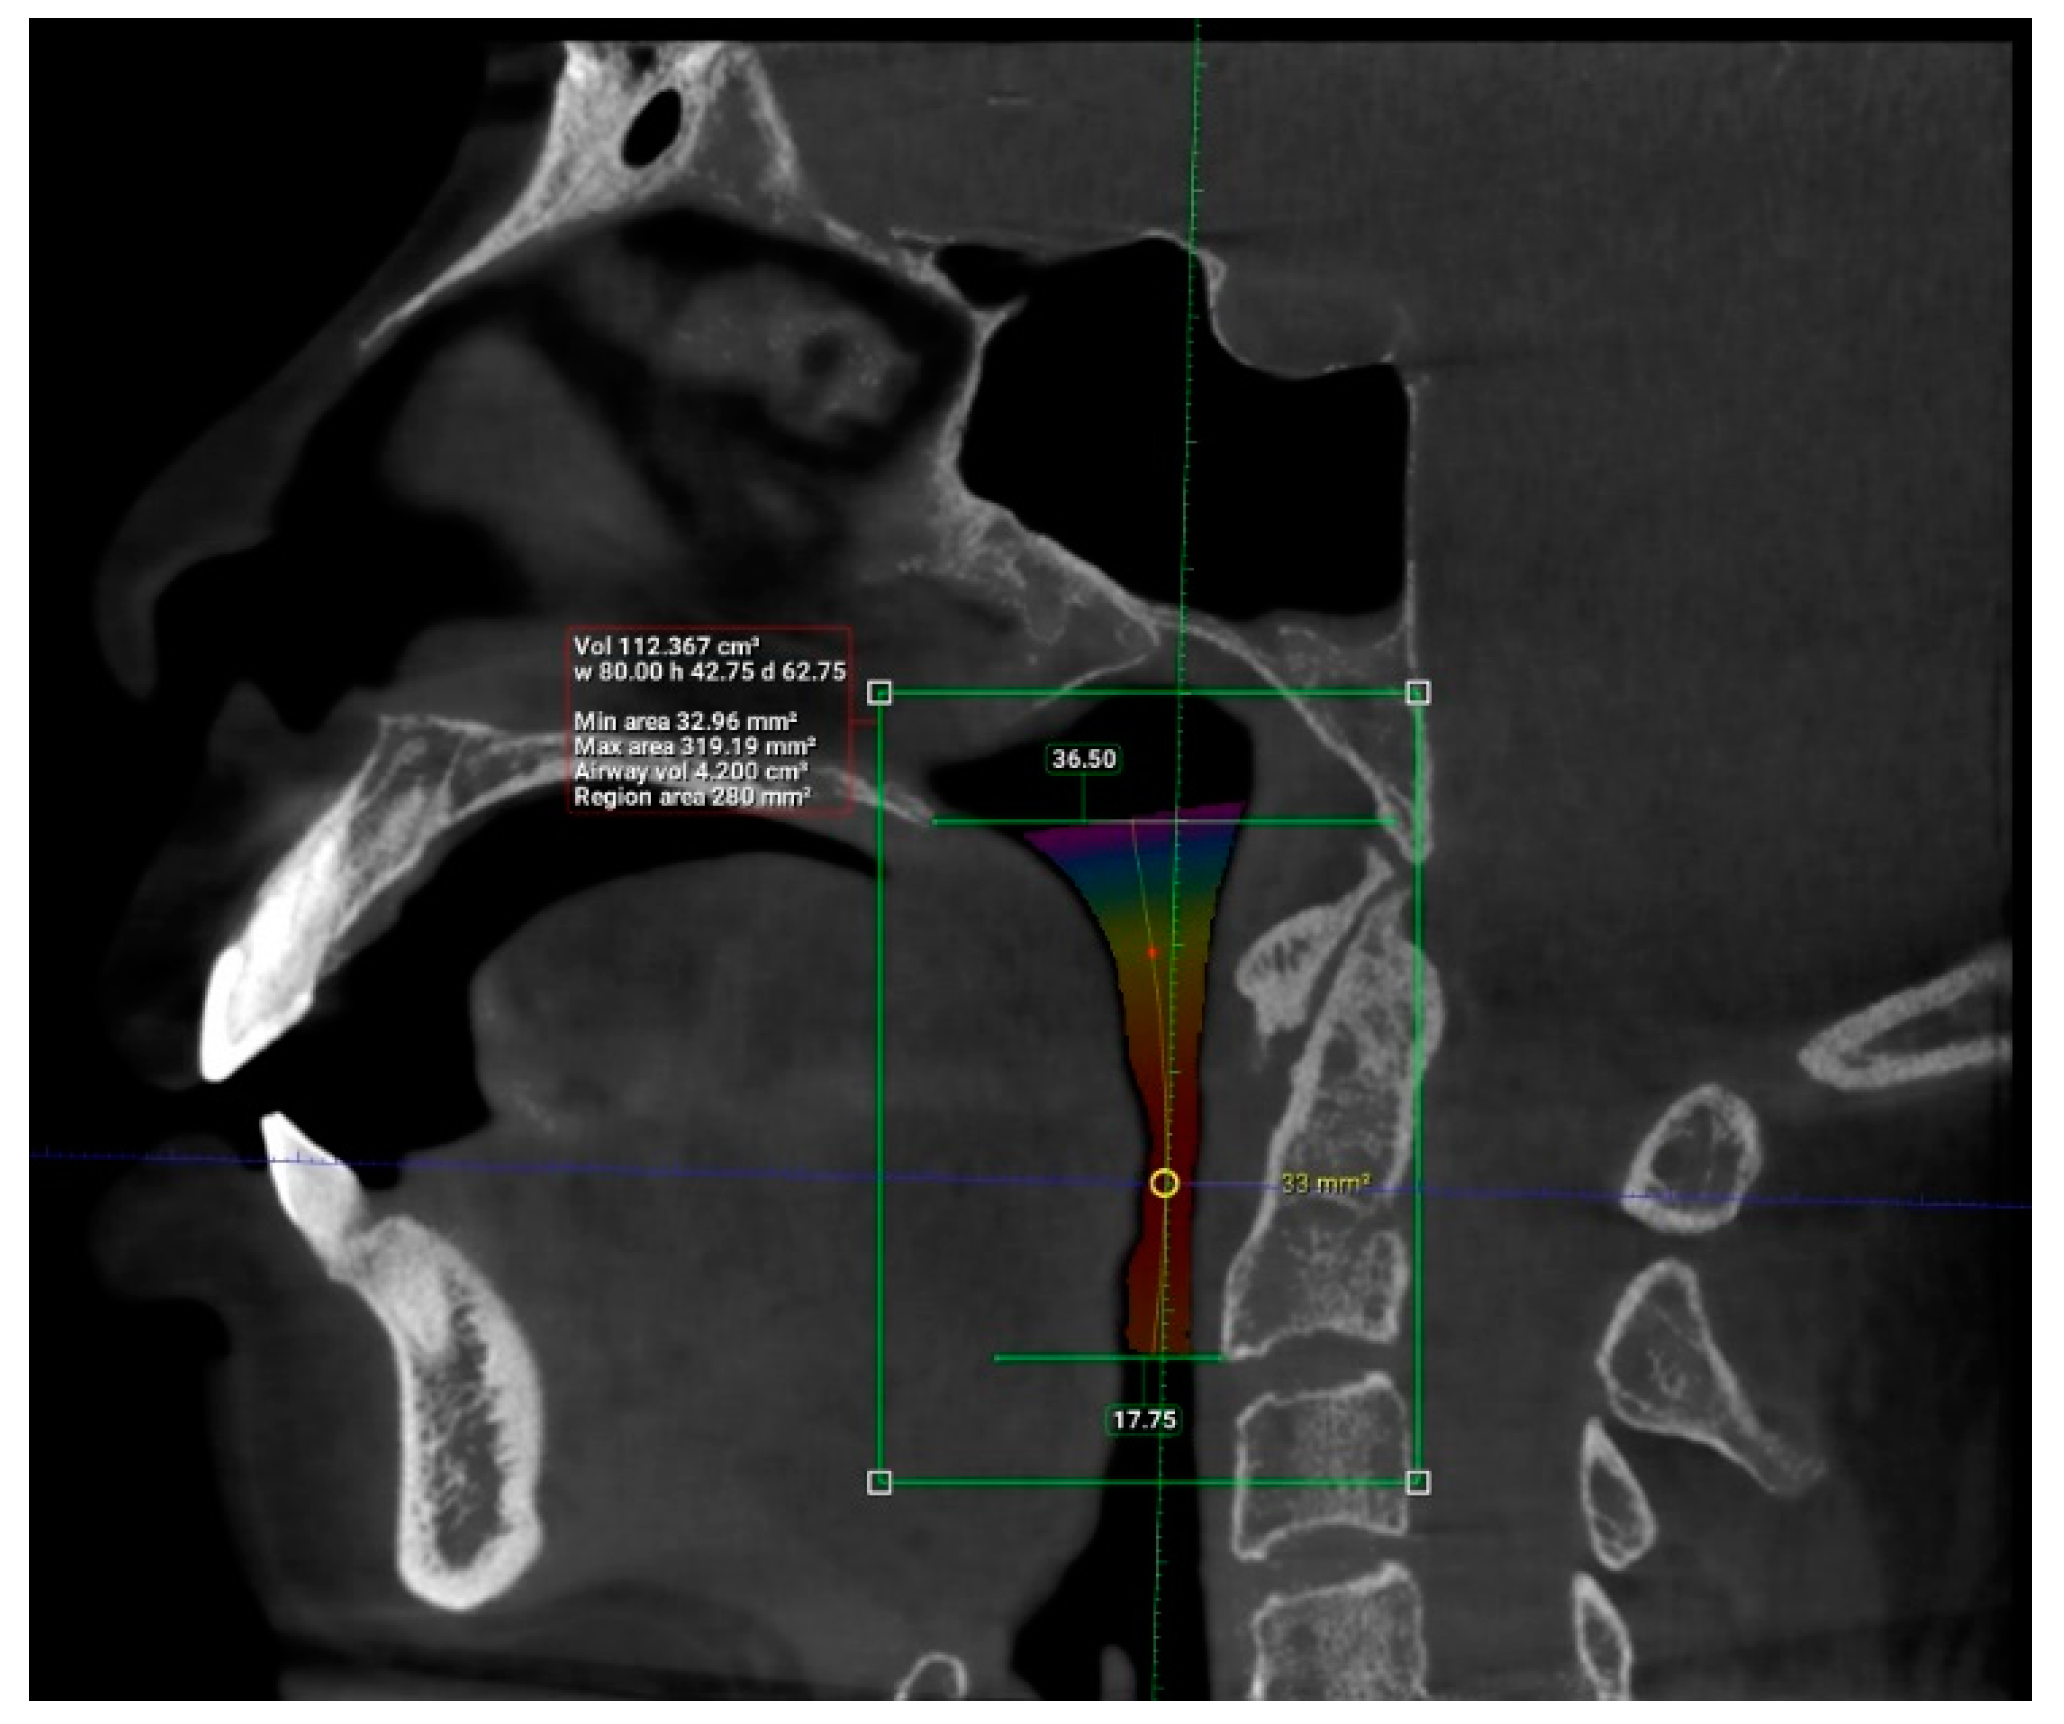

| N | Minimum | Maximum | Mean | Std. Deviation | |

| Length (mm) | 101 | 29.93 | 55.75 | 42.63 | 6.24 |

| Total volume (cm3) | 101 | 94.58 | 173.45 | 131.67 | 17.91 |

| Average volume (cm3) | 101 | 3.34 | 32.09 | 11.10 | 5.21 |

| Antero-posterior (mm) | 101 | 1.00 | 14.50 | 6.44 | 3.19 |

| Width (mm) | 101 | 8.00 | 37.00 | 21.69 | 6.54 |

| Valid N (listwise) | 101 |